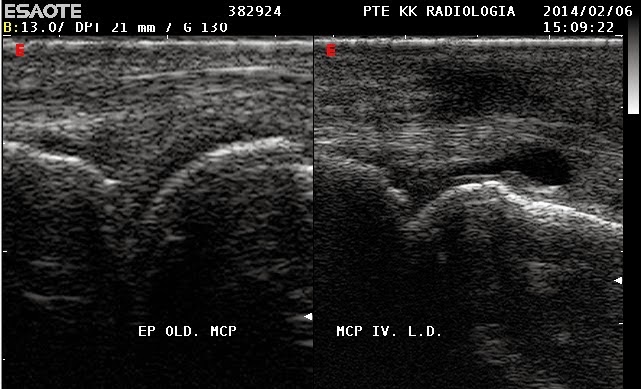

| A small amount of encapsulated fluid lies between the extensor ligament and the head of the 4th metacarpus. |

| red: extensor ligament, blue: fluid, yellow: metacarpus |

The findings above explain the pain that the patient felt flecting her MCP joint.

On flection the extensor ligament presses the fluid to the joint.